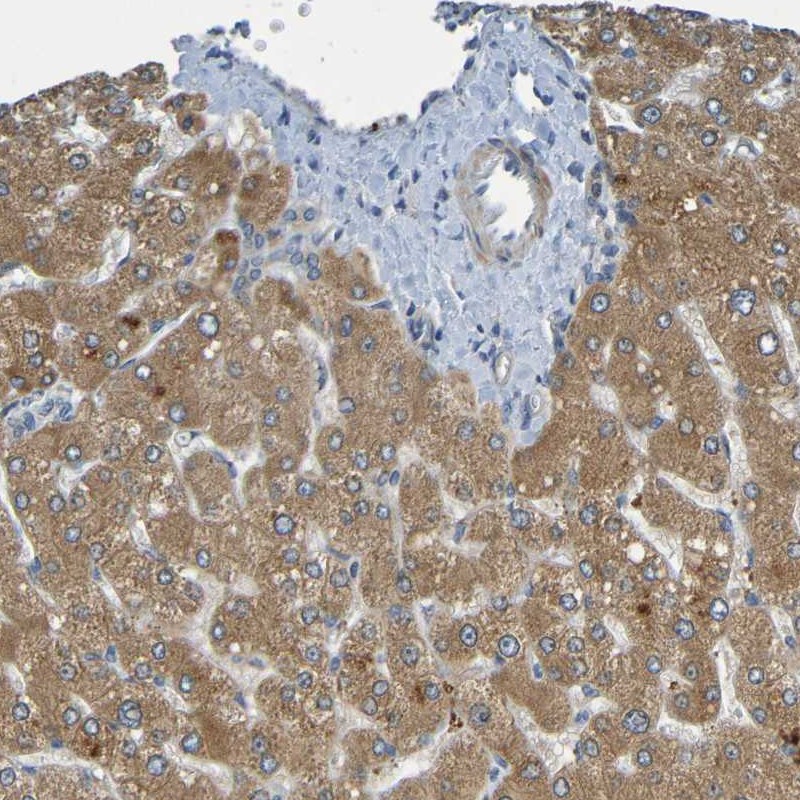

Immunohistochemical staining of human liver shows moderate cytoplasmic positivity in hepatocytes.